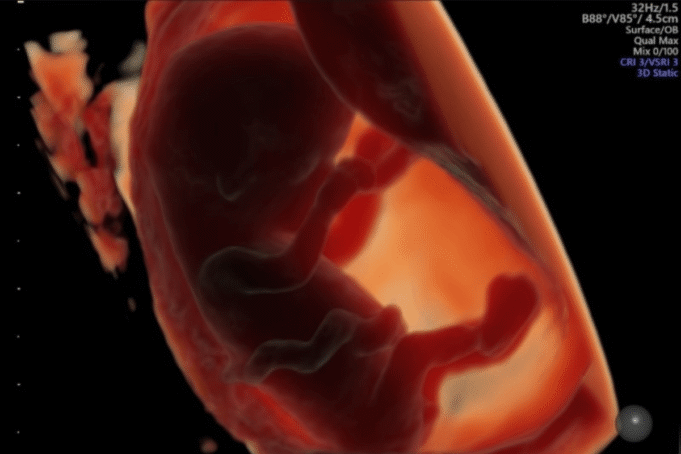

Tuttavia, un consumo più elevato è stato associato a una “lunghezza corona-groppa” più breve – una misura chiave della dimensione del feto – a sette settimane di gestazione, nonché a un sacco vitellino più piccolo, una struttura rudimentale che fornisce nutrienti al feto in via di sviluppo prima che la placenta sia completamente formata. Questi effetti sono stati più forti all’inizio del primo trimestre e sono diventati meno pronunciati successivamente.